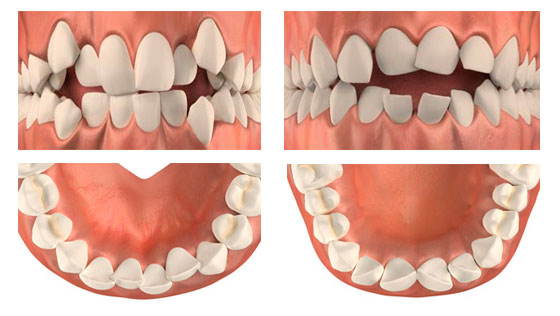

Диагноз ортодонта: скученность фронтальной группы зубов верхней и нижней челюсти, сужение и укорочение верхнего и нижнего зубных рядов. Окклюзия нормальная.

Перед началом ортодонтического лечения удалили по два зуба на верхней и нижней челюстях с обеих сторон (хирург И.И. Якименко). Согласно расчетам ортодонта удалены зубы 1.5, 2.5, 3.5, 4.4.

Для достижения поставленных целей потребовалось 2 года. Выравнивание зубов и закрытие промежутков происходило достаточно быстро. Была проведена достаточно длительная работа по достижению максимально правильных контактов верхних и нижних зубов, т.е. работа над построением нового физиологичного прикуса. Была долгая детализация наклонов зубов, доведение, так сказать, до совершенства.

Фото после снятия брекетов:

После снятия брекетов полученный результат закрепляется при помощи несъемного ретейнера, который устанавливается на центральные нижние зубы с внутренней стороны, и съемной ретенционной капы для верхних зубов, которую надевают на ночь.

Первая причина — скученность зубов. В случае незначительной скученности зубов недостающее место в зубном ряду можно получить за счет расширения зубных дуг и сепарации (пришлифовывания боковых поверхностей зубов). Если мы имеем дело с выраженной скученностью зубов, в особенности у взрослого «не растущего» пациента, для проведения ортодонтического лечения может потребоваться удаление отдельных зубов. Попытка лечения таких случаев без удаления может привести к нежелательному, зачастую неэстетичному отклонению зубов, а также спровоцировать проблемы с деснами.